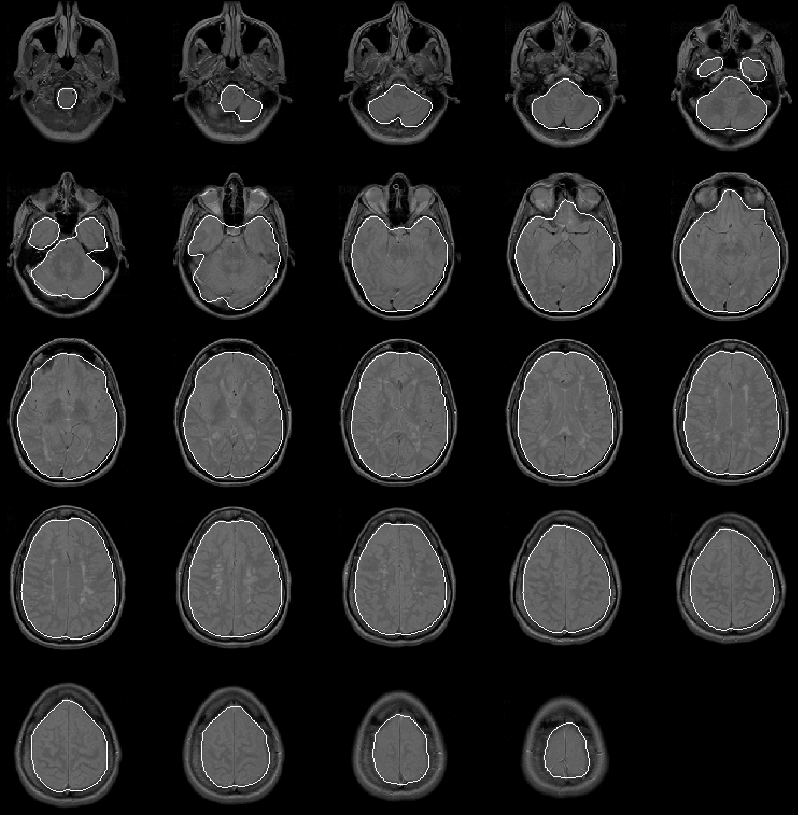

Figure 8.21: The final brain mask for MRI Data Set 2 overlaid on the PD-weighted scan.

Figure 8.21 shows the final brain mask for Data Set 2 overlaid on the PD-weighted MR scan. Again the intracranial boundary is detected exceptionally well in all slices. The final brain mask contains no remarkable errors.